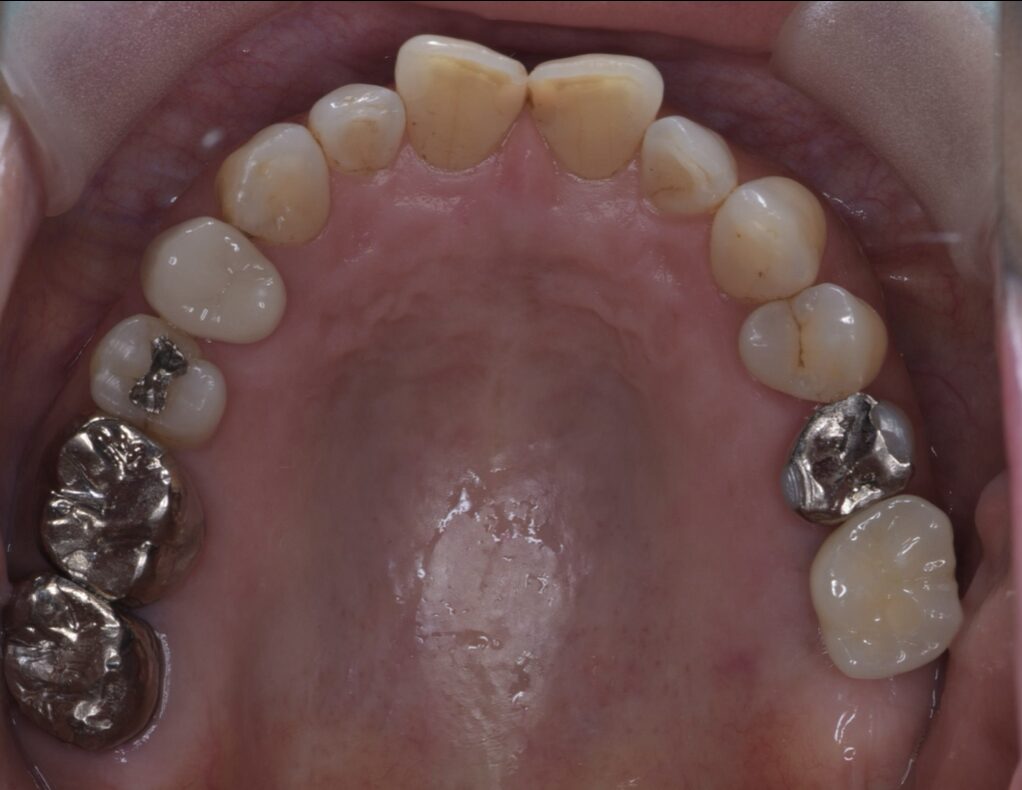

入れ歯が合わなくインプラント治療した症例

After

| 治療内容 | インプラント治療 |

| 治療期間・治療回数 | 2ヶ月半 |

| 治療費用 | 528,000円(税込) |

| リスク・副作用 | 外科処置を伴います |

| 備考 | 治療方法や費用、治療期間などは、ケースによって異なります。患者さまに合わせた治療計画をカウンセリング時にご提案いたしますので、治療例は参考程度にご覧ください。 |